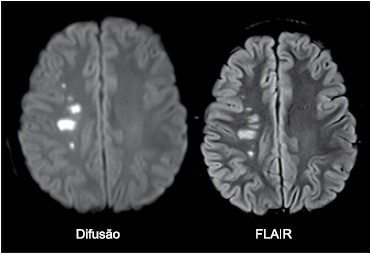

Paciente do sexo feminino, 10 anos, apresenta quadro de hemiparesia completa à esquerda de início súbito. Realizou a ressonância magnética de crânio mostrada a seguir.

O diagnóstico é